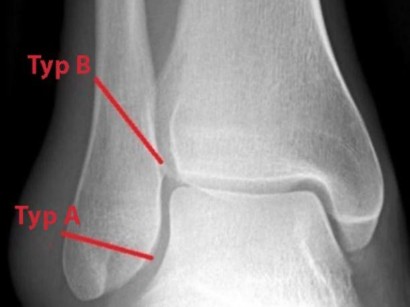

Therapie Der Radiuskopfchenfraktur Springerlink

Therapie Der Radiuskopfchenfraktur Springerlink from media.springernature.com